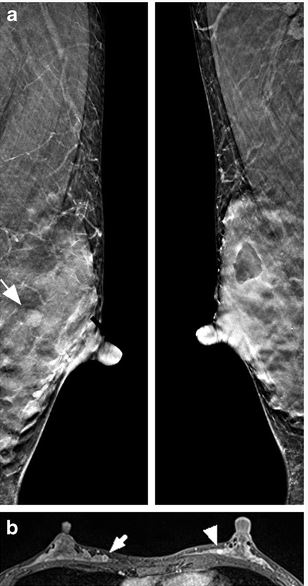

Article: The role of breast tomosynthesis in a predominantly dense breast population at a tertiary breast centre: breast density assessment and diagnostic performance in comparison with MRI

Authors: Daniel Förnvik, Masako Kataoka, Mami Iima, Akane Ohashi, Shotaro Kanao, Masakazu Toi and Kaori Togash